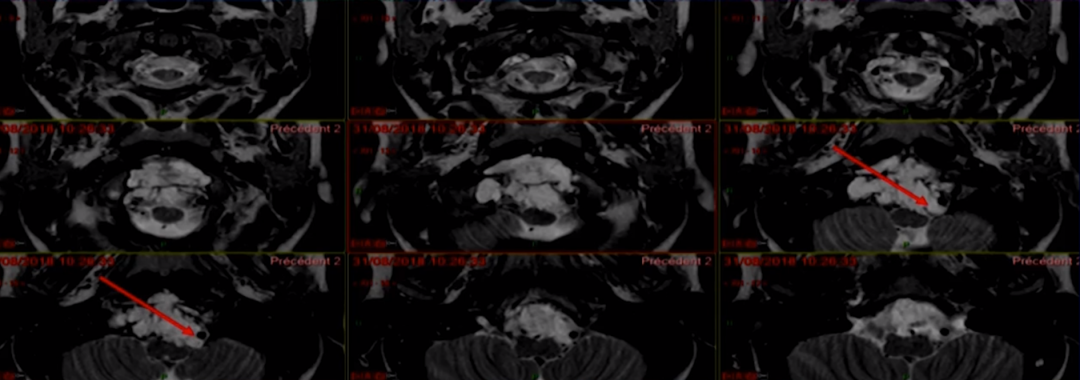

福洛里希教授运用高超的手术技术,使用前外侧入路并以进入颅颈交界区,顺利地切除肿瘤。内镜通过相对狭窄的硬脑膜开口提供宽视角,可以帮助硬脑膜内肿瘤切除(图2)。实现了肉眼全切除,术后过程很顺利,无新发神经功能缺损。术后MRI也证实了在没有并发症的情况下实现了全切。总之,内镜辅助下的前外侧入路可为颅颈交界区脊索瘤的手术治疗提供顺利合适的通道。

图2,外科手术的步骤。(A)沿胸锁乳突肌前缘切口,穿过乳突上方。(B)切除钻取枕髁和乳突后的肿瘤包膜视图。(C)从对侧颈静脉孔的神经进行硬膜内肿瘤剥离。(D)使用游离脂肪移植物闭合硬膜缺损。(E)内镜硬膜内探查显示对侧颈静脉孔有肿瘤残留,需要继续进行肿瘤切除。